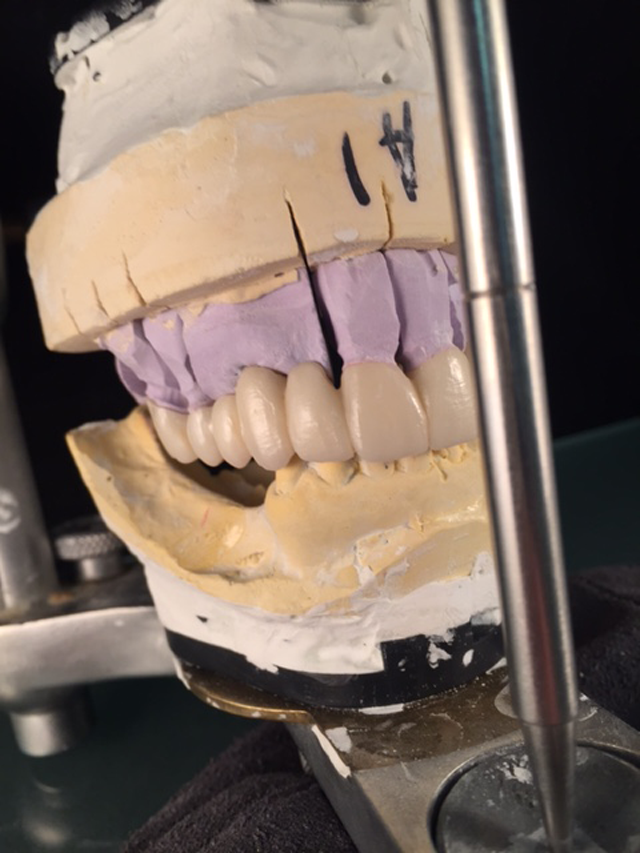

The patient no longer wanted the partial denture that she had basically learned to live with for many years; she wanted a “fixed” solution. Teeth #s 3, 4, 8, 9 and 13 were to be prepped and were our only abutments. (Figs. 1 & 2)

Fig. 1                                                                                               Fig. 2

My initial thought was to fabricate two bridges but I did not trust so few abutments and the multiple pontic spans. The doctor and I decided that a round house bridge (full upper restoration) was our best plan for success.